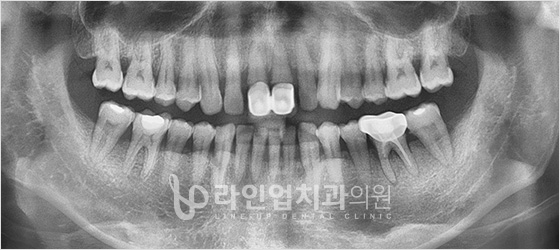

Before

After

Bottom molars implant